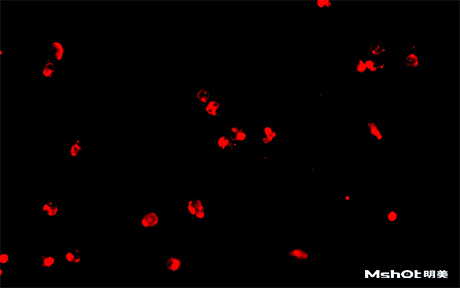

北京某试剂单位已有一台奥林巴斯生物显微镜BX61,希望能进行CTC检测,在电脑中成像拍摄保存图片,刚好我们在北京有办事处,工程师了解到具体需求分析后提供一款明美数字摄像头MS23,搭配奥林巴斯BX61生物显微镜在40X观察下,效果如图: